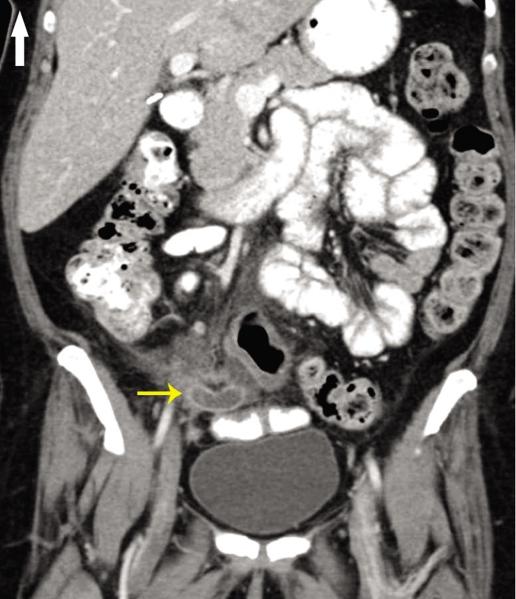

Acute appendicitis from metastatic small cell lung cancer.

https://cdn.ncbi.nlm.nih.gov/pmc/blobs/e8fe/3298197/c45ae31e7982/wjem-13-01-33w-f01.jpg